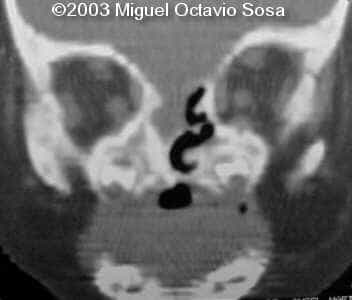

A female newborn was delivered at 38 week, by cesarean section due to breech presentation. Size of right eye is bigger than left, and there is total absence of the right nostril. Apgar 9 at birth. No complications during postpartum. Newborn is actually under study by plastic surgeon.

These are the 3D CT reconstruction.